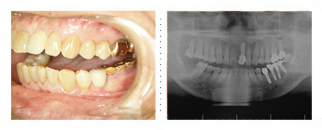

周囲の仲間からは、「インプラントの手術をすると一週間は仕事ができない」と驚かされました。第一回目の手術で4本埋め込みましたが、 本当に痛みもなく、十数分で終わってしまいました。心配していた術後の痛み・腫れ・出血も全然無く安心しました。最終的には15本のインプラントを 埋め込み、現在ではなんでも食べられ、友人と同じ様に上下全てが白い綺麗な歯になり、気持ちも若返り仕事にも活力が出ました。

最終的には上下12本のインプラントを埋め込み、全てセラミックの白い冠を被せました。 以前は食べるのが苦痛でしたが、今では食事が楽しみになり、特に固い物が噛めるようになったことが嬉しいです。よく食べられるようになったため、 痩せ気味だったのが体重も増え、近所の人やお客様からは、「まあ綺麗になったわね」と言われる様になりました。